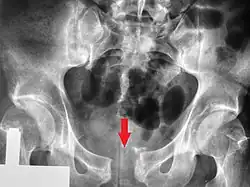

Pubic symphysis diastasis

Pubic symphysis diastasis (also known as diastasis symphysis pubis) is the separation of normally joined pubic bones, as in the dislocation of the bones, without a fracture that measures radiologically more than 10 mm. Separation of the symphysis pubis is a rare pathology associated with childbirth and has an incidence of 1 in 300 to 1 in 30,000 births. It is usually noticed after delivery but can be observed up to six months postpartum.[1] Risk factors associated with this injury include cephalopelvic disproportion, rapid second stage of labor, epidural anesthesia, severe abduction of the thighs during delivery, or previous trauma to the pelvis. Common signs and symptoms include symphyseal pain aggravated by weight-bearing and walking, a waddling gait, pubic tenderness, and a palpable interpubic gap. Treatment for pubic symphysis diastasis is largely conservative, with treatment modalities including pelvic bracing, bed rest, analgesia, physical therapy, and in some severe cases, surgery.[2]

This abnormally wide gap can be diagnosed by radiologic studies such as X-ray, Ultrasound, MRI, CT scan or bone scan. While X-Ray is the gold standard to identify a separation of the pubic symphysis, a decision must be made in regard to which imaging modality to utilize that is patient and case-specific.[3]

X-ray

An X-ray film obtained in the AP view of the pelvic inlet and outlet will show a marked gap between the pubic bones.[3] A normal pelvis will show a gap that is 4–5 mm. However, in pregnancy the hormonal influences cause relaxation of the connecting ligaments and the bones separate up to 9 mm. A gap measuring greater than 10 mm indicates a pathological process.[3]